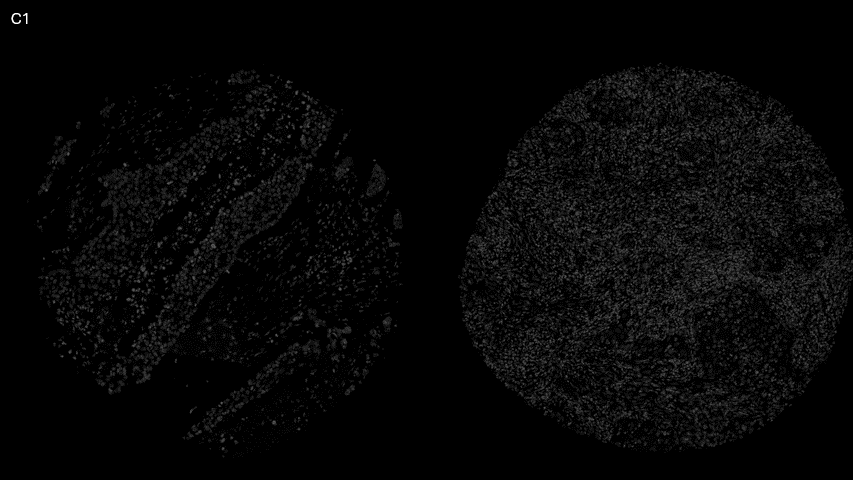

GIF: 9-plex panel on NSCLC tissue. C1) DAPI, C2) PD1/PD-L1, C3) PD1/SHP-2, C4) pEGFR, C5) GRB2/SHP-2, C6) RAF1/ERK1, C7) Fas/FADD, C8) BAX/BAK, C9) E-cadherin/ß-catenin, C10) CEACAM5

In collaboration with Uppsala University, this proof-of-concept highlights Omni’s robust performance across both cell lines and clinical FFPE samples, delivering high sensitivity and specificity while enabling simultaneous analysis of 9 targets within a single assay.